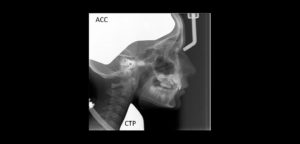

La anquilosis temporomandibular es una enfermedad que afecta a la ATM. Suele causar limitación de la apertura bucal y deformidad facial, especialmente en pacientes jóvenes.